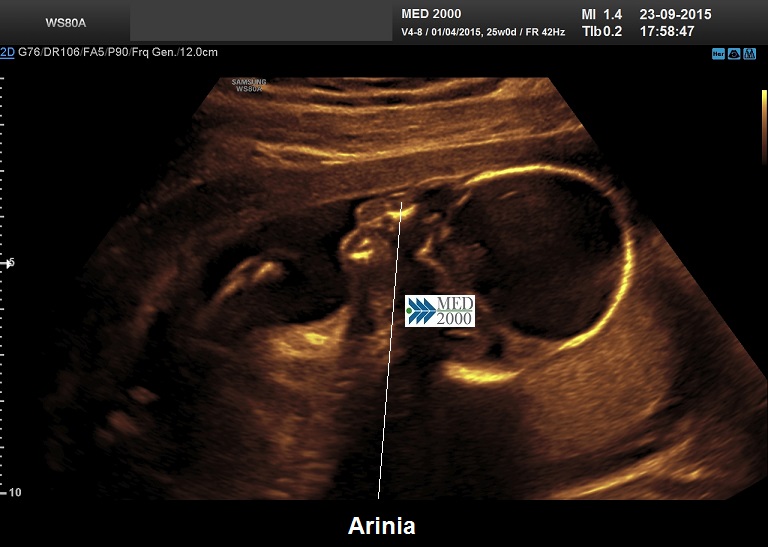

•    arinia

Le anomalie facciali sono estremamente variabili; si va da casi con gravissimi dismorfismi (caratteristici della forma alobare) a casi in cui i dismorfismi sono assenti (forma lobare).

I dismorfismi facciali sono: